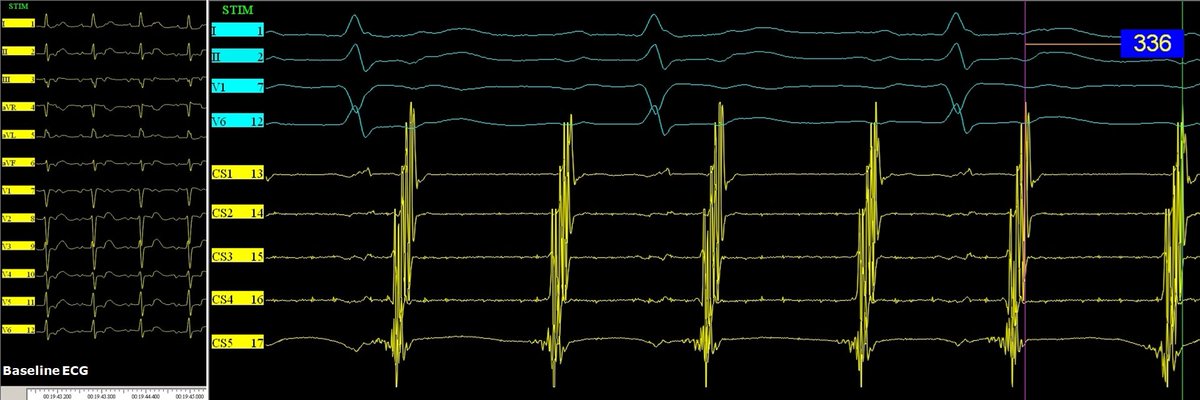

Celebrating 1yr since the publication of our Atlas of ConductSystemPacing #LBBAP #HBP! Thanks @ilpensiero for their support & to the readers for their trust! I hope it has been (& will be) useful to become confident in recognizing #CSP in your procedures! tinyurl.com/CSPAtlas